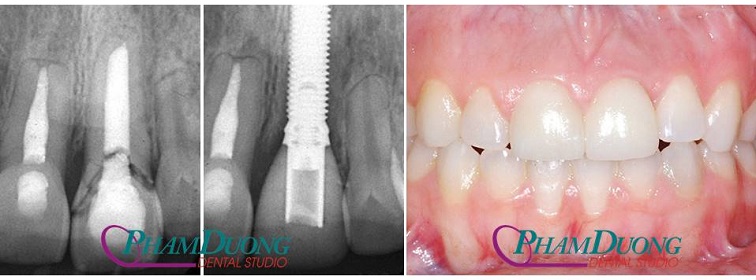

(Trường hợp răng bị nứt gãy do điều trị tủy lâu năm được cấy ghép Implant)